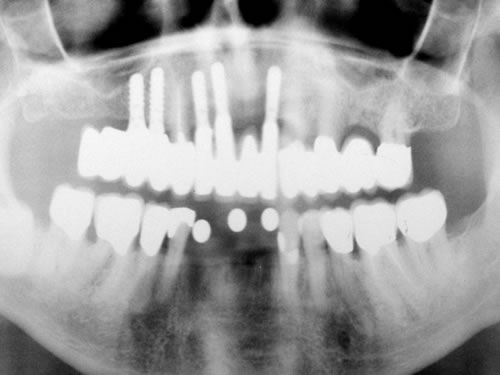

Bei der ersten Untersuchung in der Praxis hat Frau W. zunächst den Anamnesebogen ausgefüllt. Sie ist nie ernstlich krank gewesen und nimmt nur gelegentlich eine Kopfschmerztablette. In einem ausführlichen Gespräch berichtet sie ihrem Zahnarzt über die Schwierigkeiten mit den Prothesen. Nach einer ersten Untersuchung kann ihr der Zahnarzt Mut machen. Die Kieferverhältnisse sind zwar sehr ungünstig, doch so, dass eine Einpflanzung noch möglich ist. Die vorhandenen Prothesen weisen keine Mängel auf, finden aber keinen Halt. Beide Prothesen sollen nach der Einpflanzung weiter getragen werden. Nach einem Kieferabdruck wird eine Platte für den Unterkiefer angefertigt, auf der Metallkugeln befestigt sind. Sie wird wie eine Prothese eingesetzt, und es wird eine Röntgenaufnahme gemacht, die anschließend vom Zahnarzt genau vermessen wird. Es ergibt sich, dass noch eine Resthöhe von 15 mm vorhanden ist. Da auch die Breite des Kiefers ausreicht, wird ihr die Einpflanzung von vier künstlichen Zahnwurzeln empfohlen. Für ihre spezielle Kieferform ist dies die beste Lösung.

Für den Oberkiefer ist eine CT-Untersuchung notwendig, die ebenfalls mit einer Schablone durchgeführt wird. Auswertung, Planung und Implantations-Simulationen ergeben, dass sechs Implantate im vorderen Kieferabschnitt verankert werden können. Auch die Qualität des Knochens lässt eine Einpflanzung ohne weitere Maßnahmen zu. Diese Behandlung soll nach der Versorgung des Unterkiefers erfolgen.